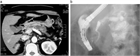

1. IPMNとは膵管内に乳頭状に発育し、多量の粘液を産生、膵管拡張を来す疾患である。主膵管型と分枝膵管型に分類され、主膵管型では主膵管のびまん性拡張像、分枝膵管型では分枝膵管の嚢胞状拡張像(ブドウの房状)が特徴である。

1. 壮年~高年男性の膵頭部に好発し、膵管との交通を認め、膵管内を進展し、随伴性膵炎を高率に合併する。